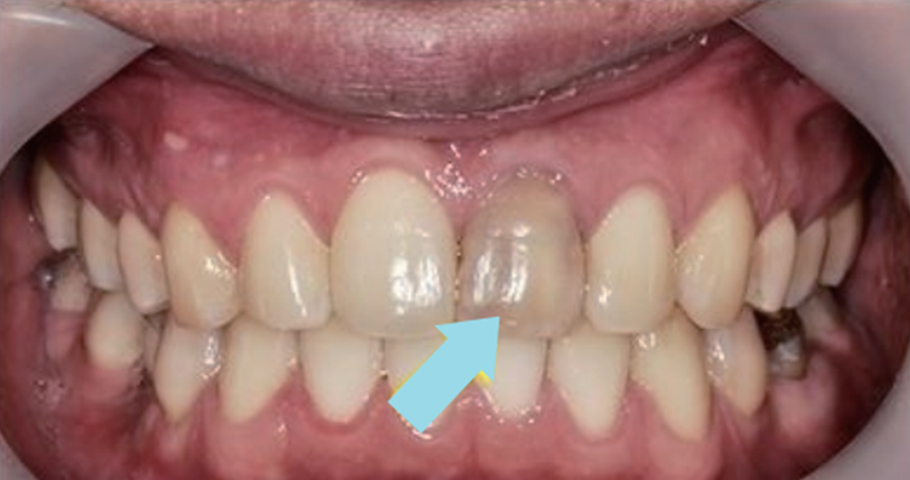

신경치료 중 치료는 마지막까지 하지 않고 방치하게 되면 치아는 신경이 없는 상태로 방치되는 것이기 때문에 까맣게 변색이 됩니다.

이런 경우 크라운이나 미백으로 회복시켜 주어야 합니다.